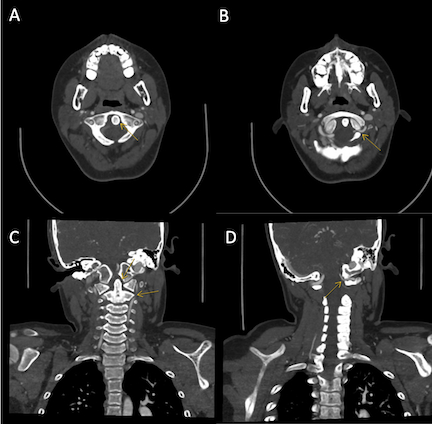

CTA demonstrated subtle narrowing of the left vertebral artery (VA) at the atlantooccipital joint with asymmetry in the position of the dens relative to the lateral masses of C1, raising concern for dynamic vessel compression. TCD with and without neck rotation and flexion/extension radiographs of the cervical spine were non-diagnostic. Given ongoing concern for rotational vasculopathy, the patient was started on aspirin 81 mg and was placed in a soft cervical collar with plans for further imaging once he had recovered from his acute stroke. Eight weeks later, he underwent contrast-enhanced MRI/MRA of the head and neck with dynamic positioning, which re-demonstrated left VA narrowing at the occipital condyle-axis joint with focal narrowing when piercing the dura. MRA in 8 positions demonstrated loss of flow-related enhancement with left head tilt and neck extension. A new area of T2 hyperintensity was visualized on MRI in the left cerebellum, likely representing an interval infarction. He subsequently underwent a C1 laminectomy without complication fourteen weeks after his initial presentation.